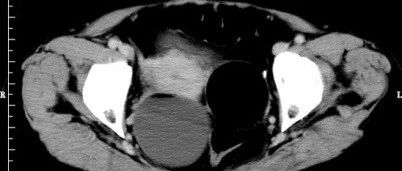

双侧卵巢畸胎瘤!

医学影像  yxyx-app  医学影像APP,打造伴随医生快速成长的影像学习社区。与影像园(Xctmr.com)一起提供最全面的影像案例库、基础(解剖、病理、影像诊断)知识、影像技术及考题等,为医生提供最佳的医学影像参考。【所属科室】普外科【基本资料】患者,女,71岁【主诉】B超发现盆腔肿块一天【影像图片】【讨论问题】如何诊断?【医学影像APP用户讨论】评论:...